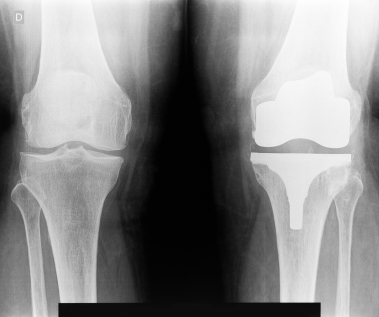

Артрография

Описание услуги - Артрография

Артрография осуществляется наметить суставы и связки. Краситель вводится в сустав и рентгеновские лучи приняты с целью выявления любых травм.